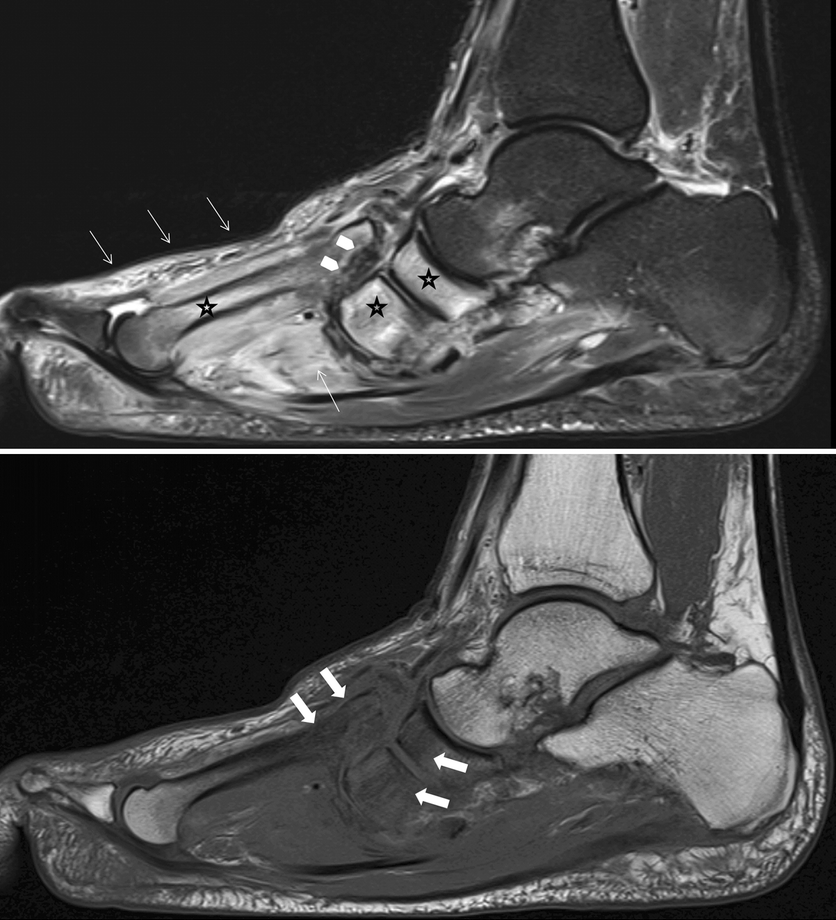

МРТ стопы при псориатическом артрите. Отек, воспаление, патологическое контрастирование суставных капсул, синовиальных оболочек

МРТ при плантарном фасциите. Хорошо видны воспаление и отек подошвенного апоневроза.